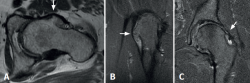

Figura 2. A y B: corte axial de resonancia magnética (RM) en secuencia T1 (A) y corte coronal de RM en secuencia T2 (B) que evidencian una exostosis ósea de gran tamaño en la superficie anterolateral del cuello femoral; C: corte coronal en secuencia T2 que evidencia exostosis en el cuello femoral y signos compatibles con rotura del labrum anterosuperior.